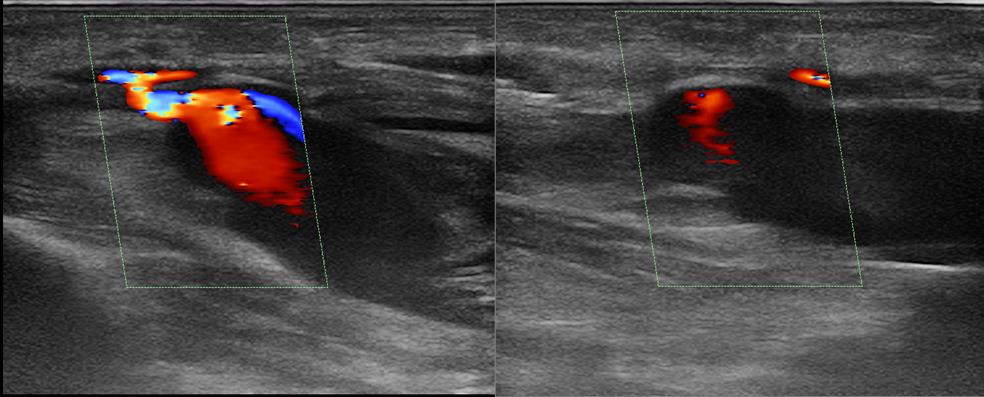

Repeat duplex scanning of the upper limb arteries: the aneurysm cavity spread to the upper third of the upper arm (Figures 3, 4), with the main type blood flow through the RA. Under ultrasound guidance, compression was applied in the area of the pseudo-aneurysm neck.

Fig. 3. Repeat Duplex scan (the second day), color Doppler mode, longitudinal section. The blood flow in the lumen of the radial artery pseudoaneurysm is shown.

Fig. 4. Repeat Duplex scan (the second day), spectral Doppler mode, longitudinal section. The blood flow in the neck of the radial artery pseudoaneurysm is shown.